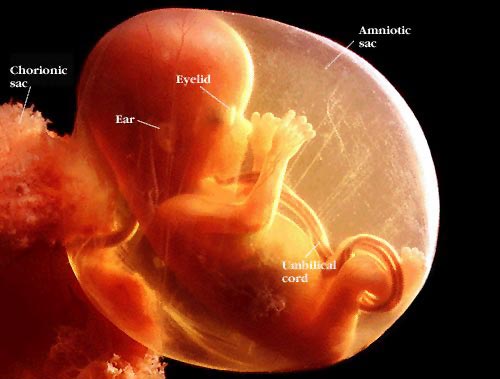

طول جنينك:

يبلغ طوله في اول الشهر السابع34 سم اما وزنه فكيلو غرام واحد فقط!

في نهاية الشهر السابع سيبلغ طوله 27 سم ووزنه 1,5 كغ, ويصل قطر رأسه الى8,2 سم

مازال طفلك يمص اصبعه وقد يبدو ابهام بعض الاطفال شديد الاحمرار عند الولادة لفرط مامصٌوه بنهم .

العينان:

في الاسبوع التاسع والعشرين يفتح طفلك عينيه كليا لكن شبكية العين تبقى عاطلة عن العمل لان النور لايصل اليها وفي هذه المرحلة الرموش تزداد طولاً.